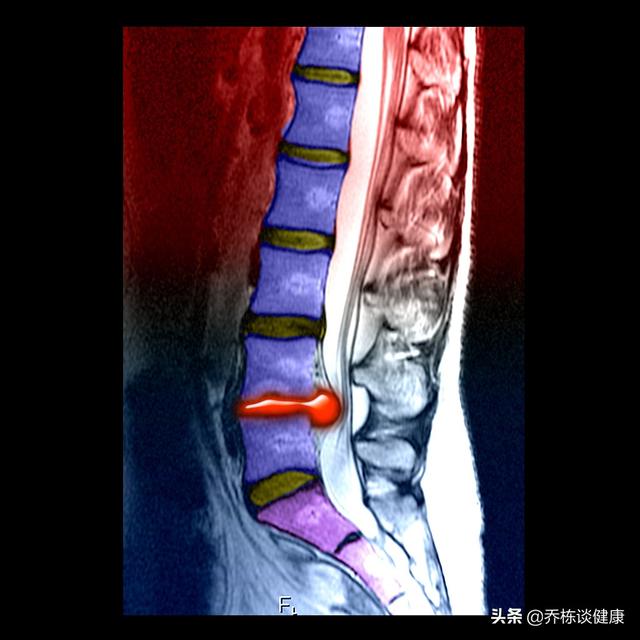

腰部脊柱管狭窄症とは、脊柱管の直径が小さくなることを言いますが、例えば、生まれつき脊柱管が狭かったり、骨棘や腫瘍が原因であったり、もちろん最も一般的なのは、腰椎椎間板ヘルニアが原因で脊柱管狭窄症になるなど、非常に多くの要因によって引き起こされる可能性があります。

腰部脊柱管狭窄症は現象であり、腰部脊柱管狭窄症疾患は病気である。腰部脊柱管狭窄症の症状は?主な症状は、腰部の痛みやシビレ、脱力感、足のしびれや脱力感で、最も典型的な症状は間欠性跛行、つまり歩けば歩くほど足が痛くなったり脱力したりするので、しゃがんだり前かがみになったりしてそれを和らげてから歩き続けなければなりませんが、一方、このような状況は自転車に乗っていても何の違和感もなく、好きなことができます。なお、腰部脊柱管狭窄症では脚の痛みは起こらず、脚の痛みは腰椎椎間板ヘルニアで見られるのが普通です。両者の違いは簡単で、直立挙上テストをすると、腰部脊柱管狭窄症はできる、腰椎椎間板ヘルニアは断じてできない。